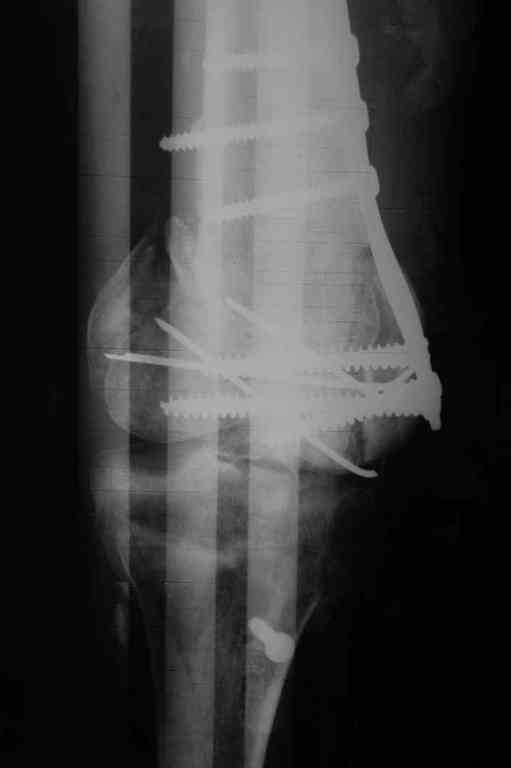

Re: Последствия открытого перелома дистального отдела бедра

Пожалуйста, снимки.